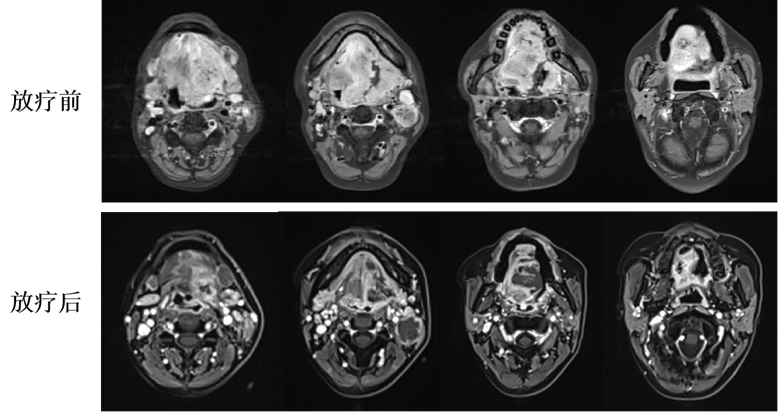

放療前后復(fù)查口腔核磁對(duì)比圖像

圖注:上排治療前,可見腫瘤范圍特別巨大,全舌受侵,整個(gè)口底、上顎受侵,基本占據(jù)整個(gè)口腔;同時(shí)腫物向后侵犯口咽,并侵占口咽腔,病灶明顯強(qiáng)化。雙側(cè)頸部可見多發(fā)淋巴結(jié)轉(zhuǎn)移。下排治療后,腫瘤縮退良好,侵犯范圍明顯縮?。晦D(zhuǎn)移淋巴結(jié)內(nèi)部已完全液化。